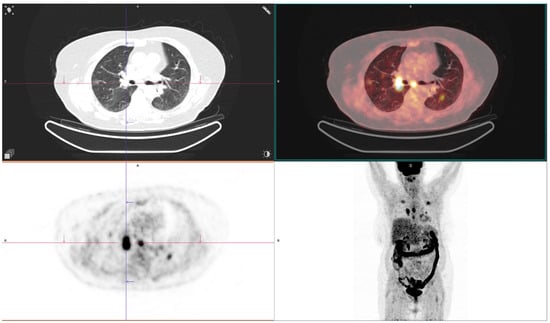

| Metastases present, n (%) | 3 (9.4%) | 7 (25.0%) | 0 (0.0%) | 8 (61.5%) | 0 (0.0%) | <0.001 | Acinar vs. solid | na | na | 0.001 |

| Lepidic vs. solid | na | na | <0.001 | |||||||

| Solid vs. AIS-MIA | na | na | 0.003 | |||||||

| SUVmax, mean ± SD | 4.9 ± 1.1 | 5.3 ± 1.3 | 5.1 ± 0.7 | 6.3 ± 0.8 | 3.3 ± 0.8 | <0.001 | Acinar vs. solid | −1.35 | −1.89 to −0.76 | 0.001 |

| Acinar vs. AIS-MIA | 1.65 | 1.00 to 2.28 | <0.001 | |||||||

| Papillary vs. AIS-MIA | 2.01 | 1.35 to 2.72 | <0.001 | |||||||

| Lepidic vs. AIS-MIA | 1.83 | 1.23 to 2.38 | <0.001 | |||||||

| Solid vs. AIS-MIA | −3 | 2.32 vs. 3.59 | <0.001 |